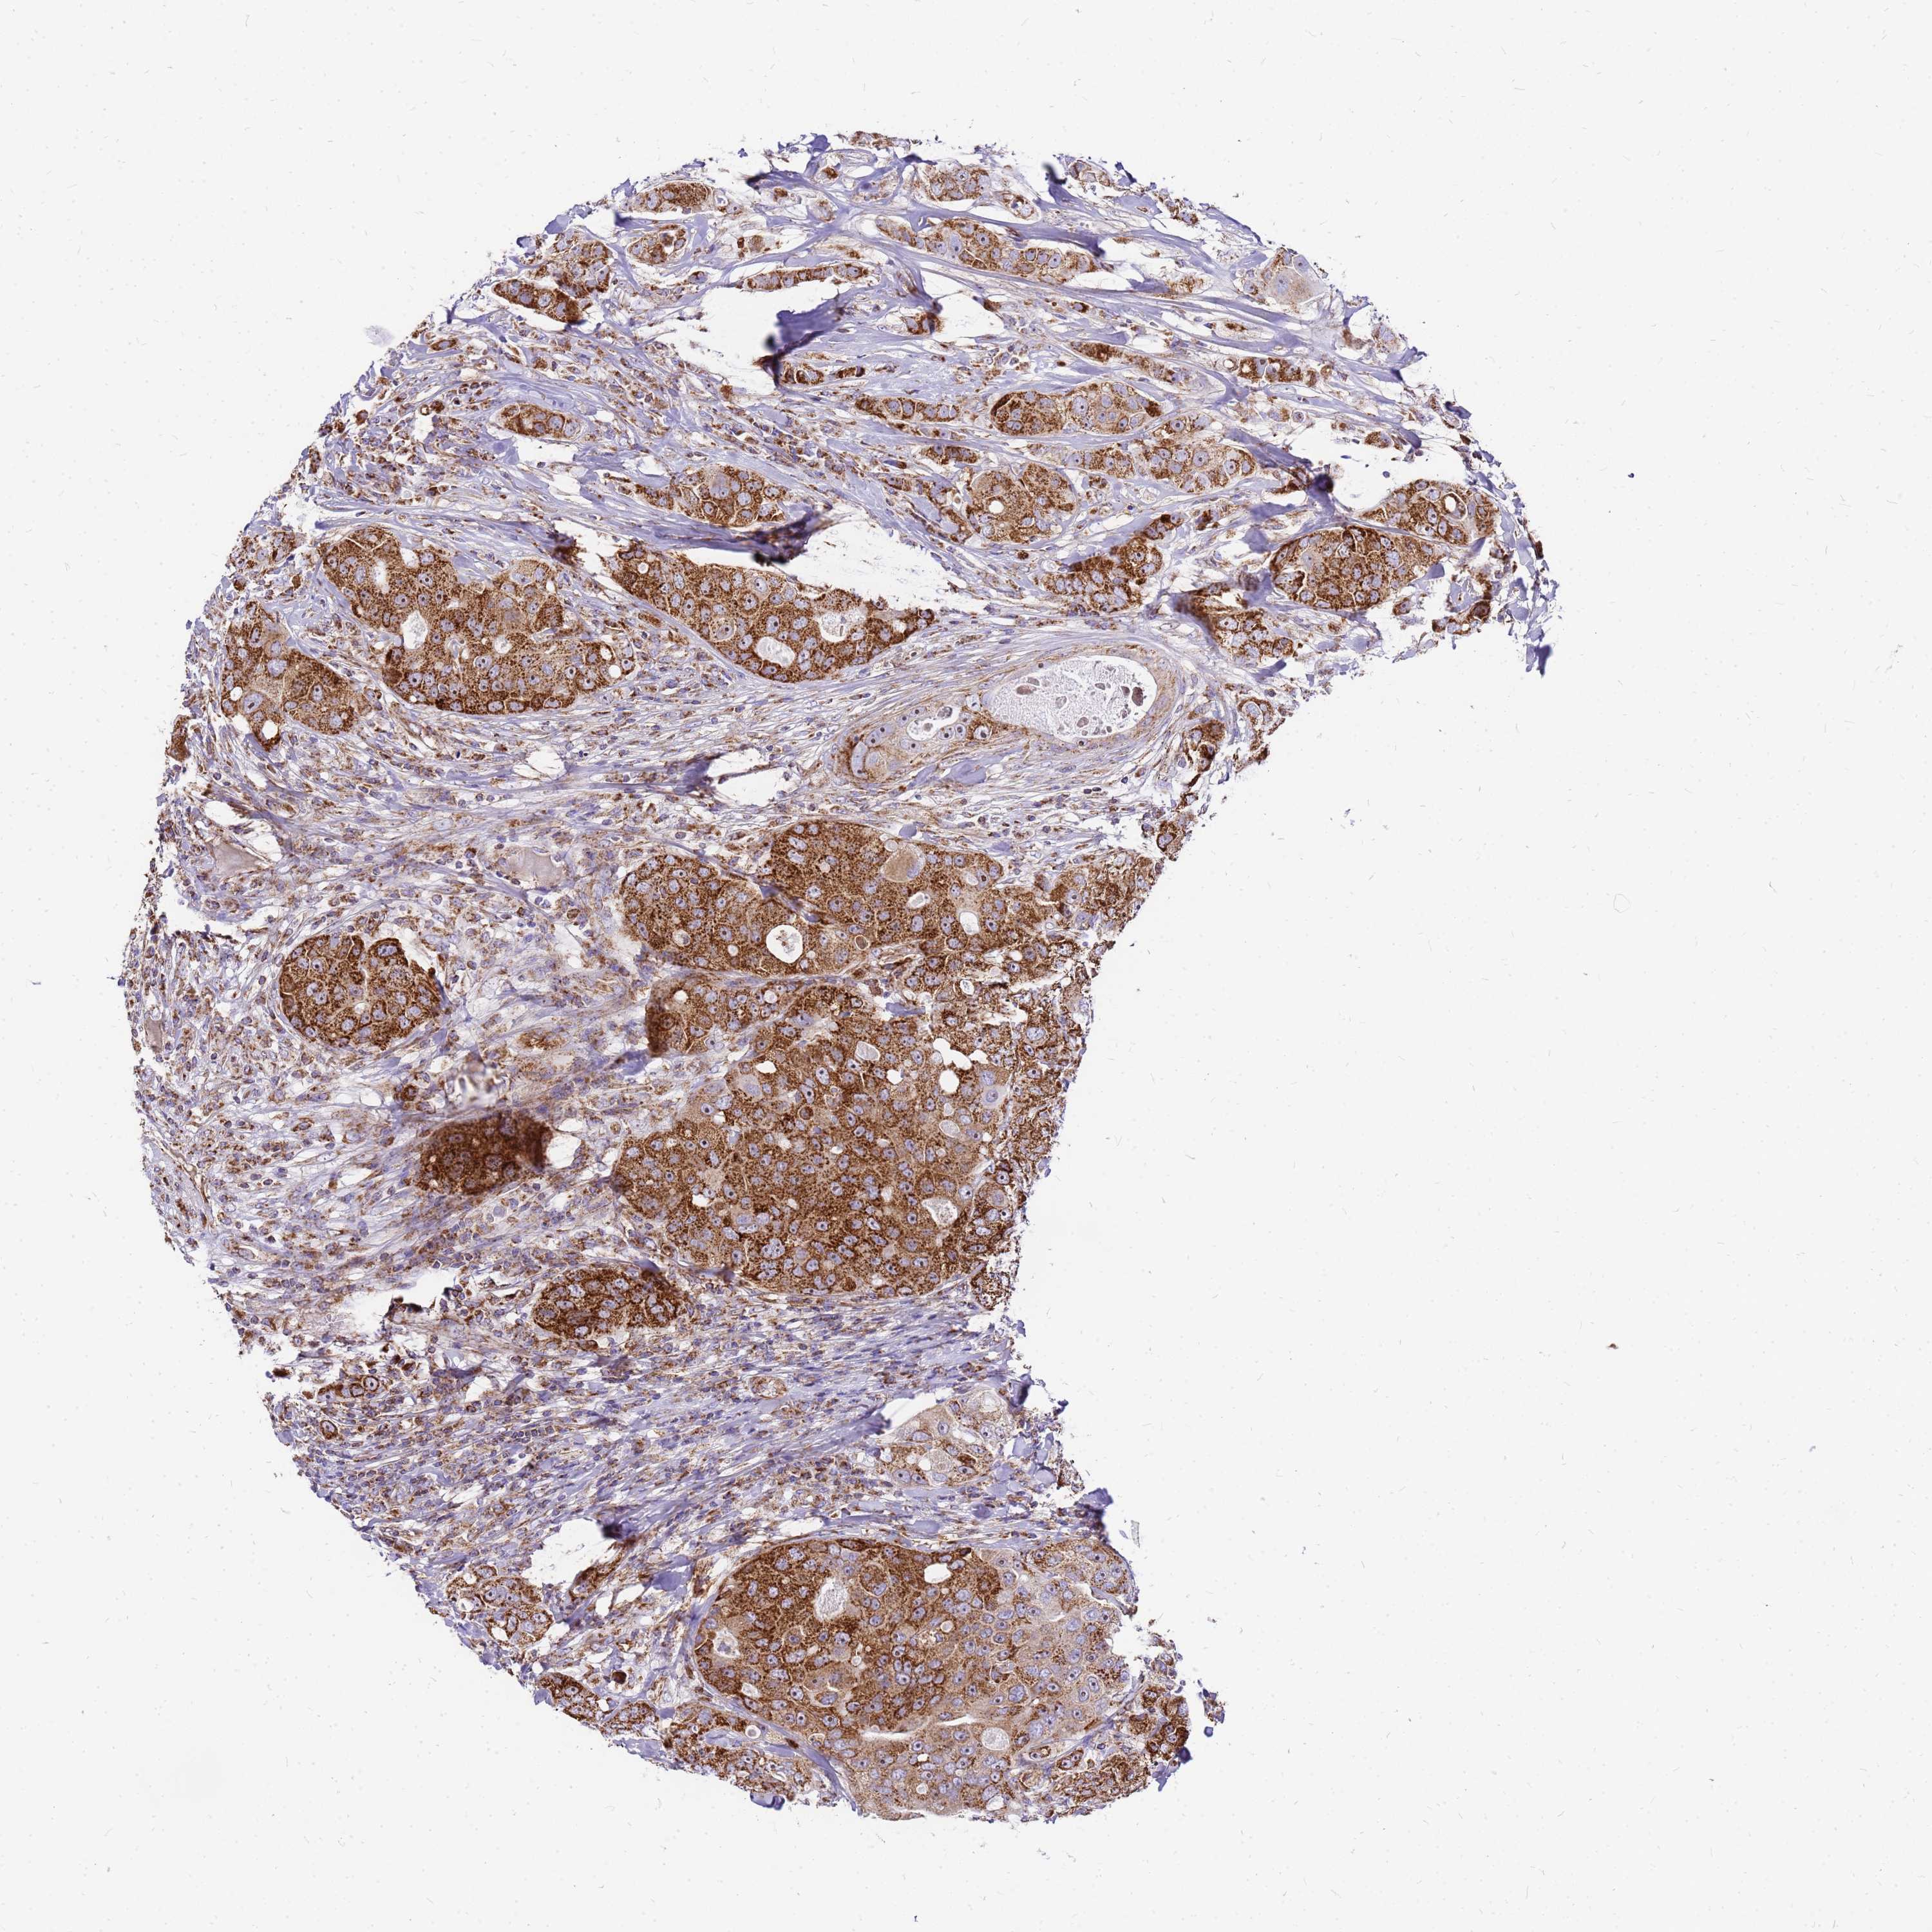

CANCER BREAST CANCER Show tissue menu

BRCA TCGA BRCA VALIDATION PROTEIN EXPRESSION

MRPS26 is not prognostic in Breast Invasive Carcinoma (TCGA)